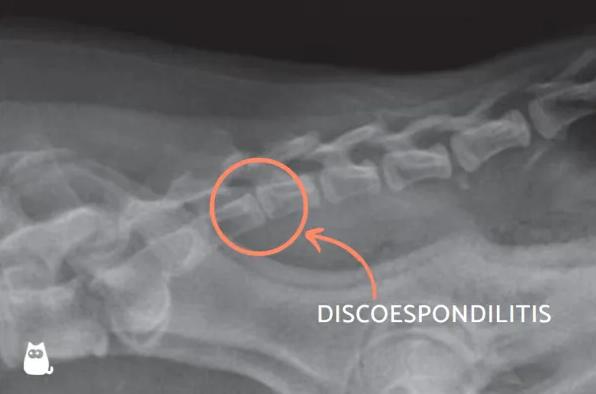

Infección vertebral

Si has pronunciado la frase "mi perro chilla de dolor de repente" puede ser que presente una infección vertebral. La infección en las vértebras se denomina discoespondilitis por ser un proceso infeccioso que ataca a los discos intervertebrales, lo que acaba por producir una deformación ósea además de una irritación e inflamación que puede comprimir la médula espinal, provocando un fuerte dolor e incluso alteraciones de la marcha o cese de la movilidad.

Los discos invertebrales son una especie de amortiguadores entre vértebras para que no se rocen entre sí. Se infectan cuando son alcanzados por microorganismos, generalmente pertenecientes a la cavidad oral, al aparato respiratorio, las válvulas cardíacas, la piel, el aparato respiratorio o el genitourinario. Descubre todos los detalles aquí: "Discoespondilitis en perros - Síntomas y tratamiento".